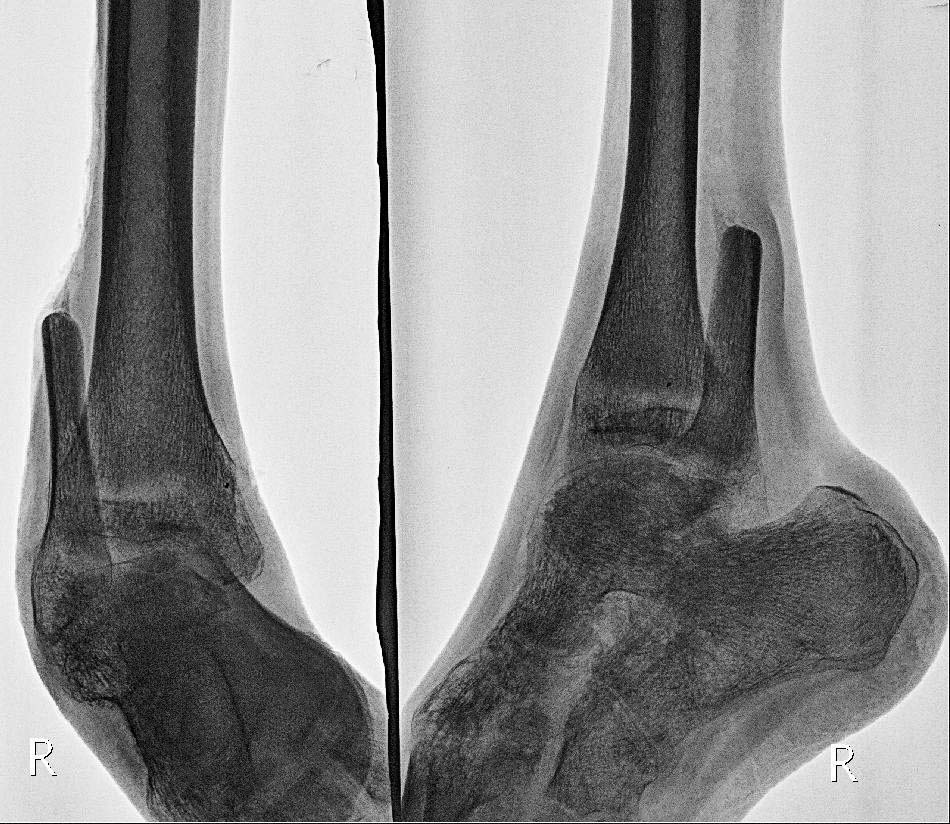

Вложение не в текстовом формате было извлечено…

Url     : http://weborto.net:8080/pipermail/ortho/attachments/20150221/1b434c5b/attachment-0005.jpg